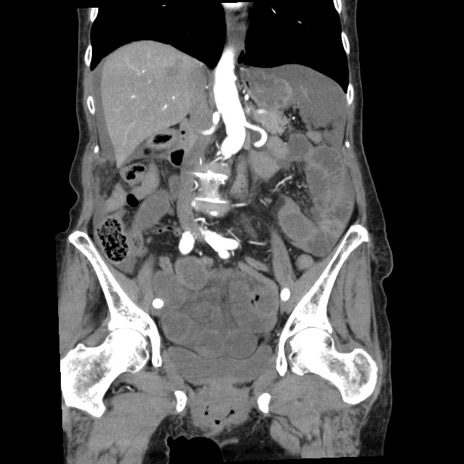

症例1(冠状断像)

【症例】80歳代女性

【主訴】腹痛

【現病歴】8時間前から腹痛あり来院。

【既往歴】糖尿病、脂質異常症、子宮体癌にて子宮全摘術

【身体所見】意識清明・会話良好だが腹痛で苦悶様、全腹部にわたって反跳痛と圧痛あり

【データ】WBC 13600、CRP 0.14、LDH 224、CK 90